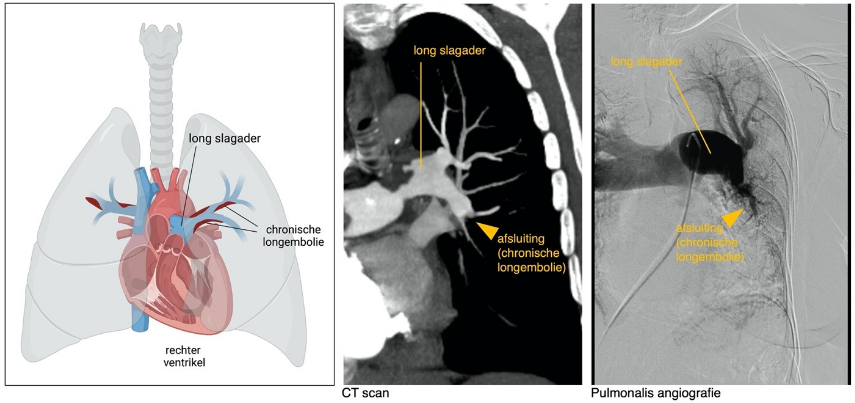

De onderzoeken die gedaan worden om CTEPH vast te stellen, komen grotendeels overeen met de onderzoeken die bij andere vormen van pulmonale hypertensie worden gedaan. Om de drukken te meten wordt rechtscatheterisatie gedaan, de conditie wordt in kaart gebracht met een fietstest (ergometrie) of een 6-minuten looptest. Bij CTEPH worden extra onderzoeken gedaan om de stolsels goed in kaart te brengen. Dit kan bijvoorbeeld door toediening van contrast tijdens de rechtscatherisatie. Dit wordt ook wel een pulmonalis angiografie genoemd, en geeft een afbeelding van de longbloedvaten en van verstoppingen. De verstoppingen kunnen ook in beeld worden gebracht door middel van een CT scan, waarbij contrast wordt toegediend. Deze onderzoeken zijn nodig om vast te stellen hoe de CTEPH het best behandeld kan worden.